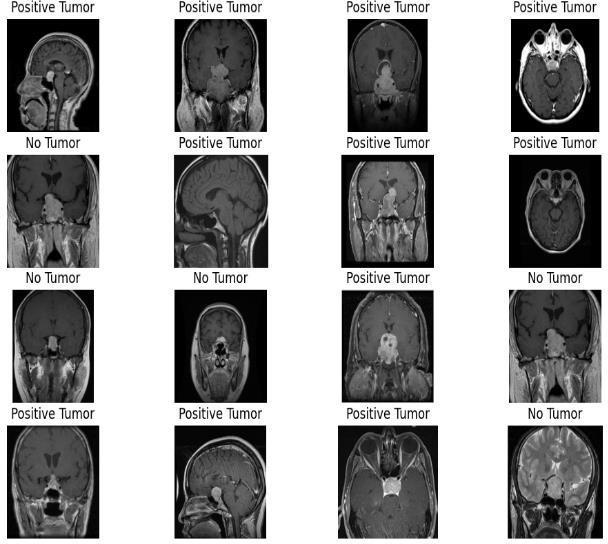

Fig.3.Samplestestedforpituitarytumor.

Fig 3 shows results of testing of SVM model on the testingdataofchosendatasetforpituitary tumor.

Fig.4.TestingResults.

After testing the model, we got the training score of 0.9887andtestingscoreof0.9592.